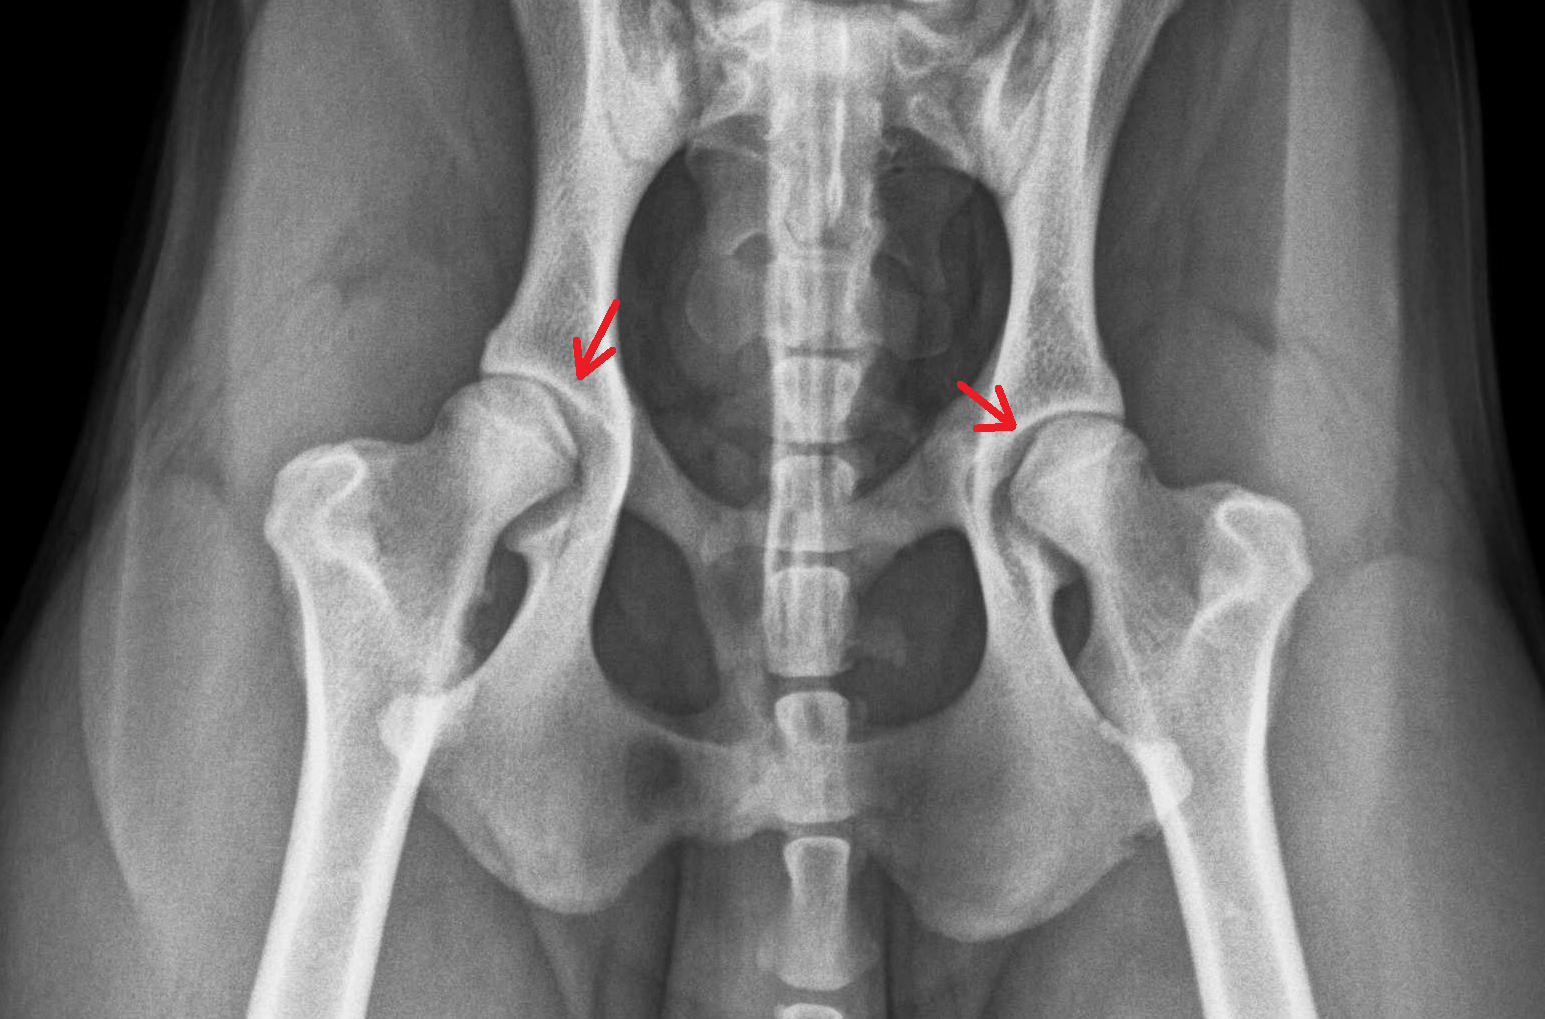

- Hüftdysplasie (HD)